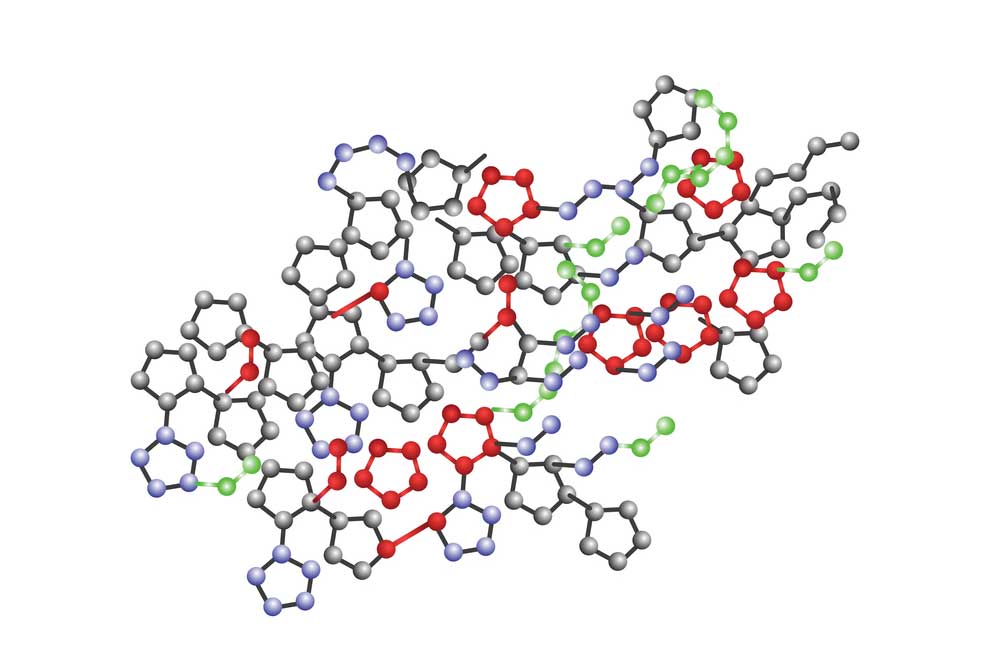

نغطي كل التخصصات الطبية

استیعاب کافة الحالات الطبیة لشمولیة التخصصات